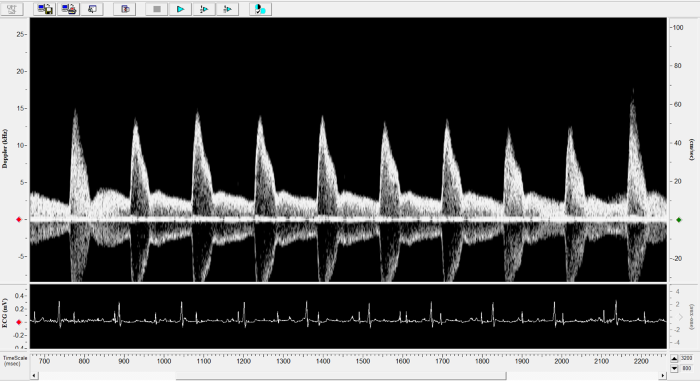

Pulmonary Flow

Pulmonary Flow. Image Credit: Scintica Instrumentation Inc.